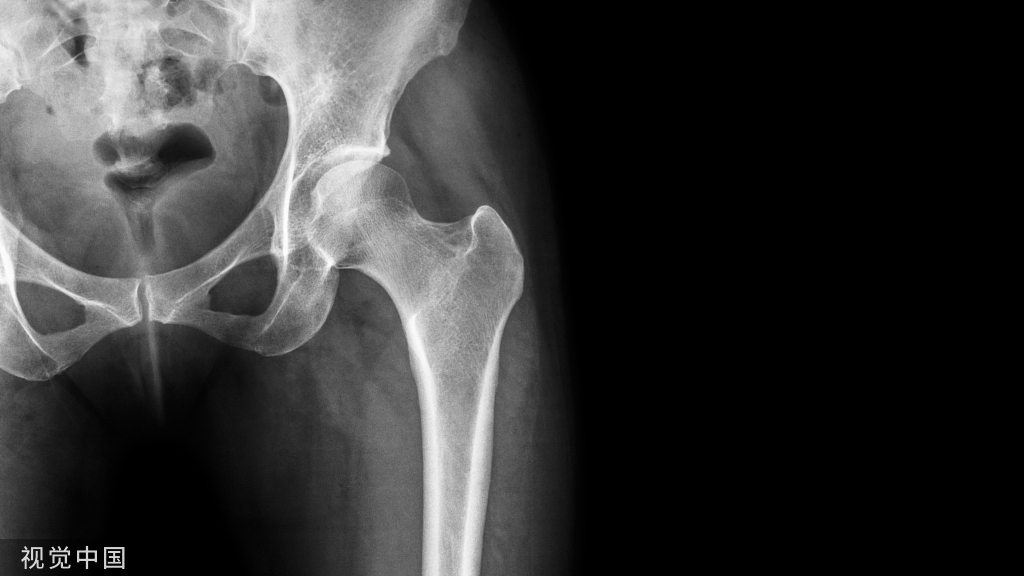

颈干角和前倾角最能体现髋关节的结构功能特征。

①颈干角:股骨颈与股骨干纵轴所形成的倾斜角为颈干角或内倾角。正常范围为110°~140°成年时平均为127°。 超过此角度的变形成为髋外翻(caxa valga),小于此角度者称之为髋内翻(coxa vara)。

②前倾角:股骨颈的轴线与股骨内外髁的髁间连线间有一向前扭转的角度,称为前倾角,成人一般不超过10°~12°,正常值在正常值在12°~15° 。

股骨上端的骨小梁系统

股骨头上端主要形成四组骨小梁,其排列方向沿股骨的主应变方向(有三组抗压骨小梁群基本上平行于股骨长轴方向,交织着由下方向上方走行,以保证股骨的强度和韧性,对抗体重的的重力;而主抗张骨小梁群的骨小梁则起到对抗横向张力的作用),从而最大限度地减少剪力: